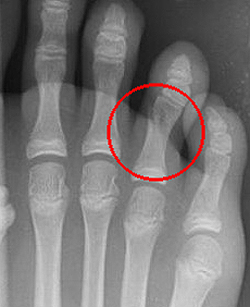

Переломы фаланг пальцев стопы

Эта разновидность переломов костей стопы, как правило, возникает при прямом воздействии травмирующей силы (падение тяжести, удар по пальцам). Переломы средней и ногтевой фаланг пальцев в последующем не нарушают функцию стопы. Неправильное сращение переломов основных фаланг может приводить к развитию посттравматических артрозов плюснефаланговых суставов, ограничению подвижности и болям при ходьбе.

Травмированный палец синюшен, отечен, резко болезненен при движениях, ощупывании и осевой нагрузке. Переломы ногтевой фаланги часто сопровождаются образованием подногтевой гематомы. Для подтверждения переломов фаланг выполняют рентгенограммы в 2-х проекциях.

При переломах фаланг пальцев стопы без смещения накладывают заднюю гипсовую шину. При смещении отломков выполняют закрытую репозицию. Костные фрагменты фиксируют спицами. При переломах ногтевой фаланги без смещения возможна иммобилизация с использованием лейкопластырной повязки. Срок фиксации зависит от тяжести перелома и составляет от 4 до 6 недель.